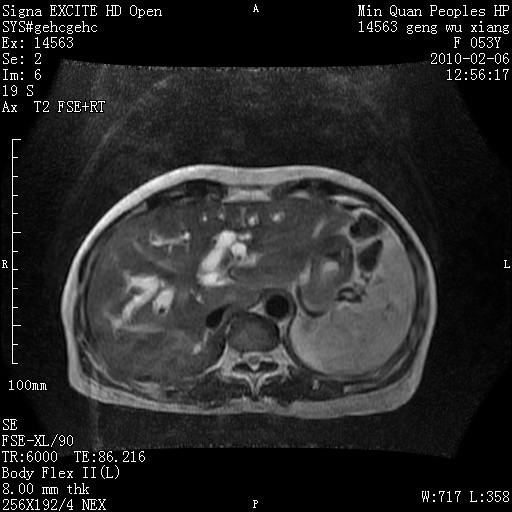

标题: MRI2762:胆道梗阻原因?

f,53y,全身黄染多日。

高位胆道梗阻 胆管癌可能性大

支持 高位胆道梗阻 胆管癌可能性大。